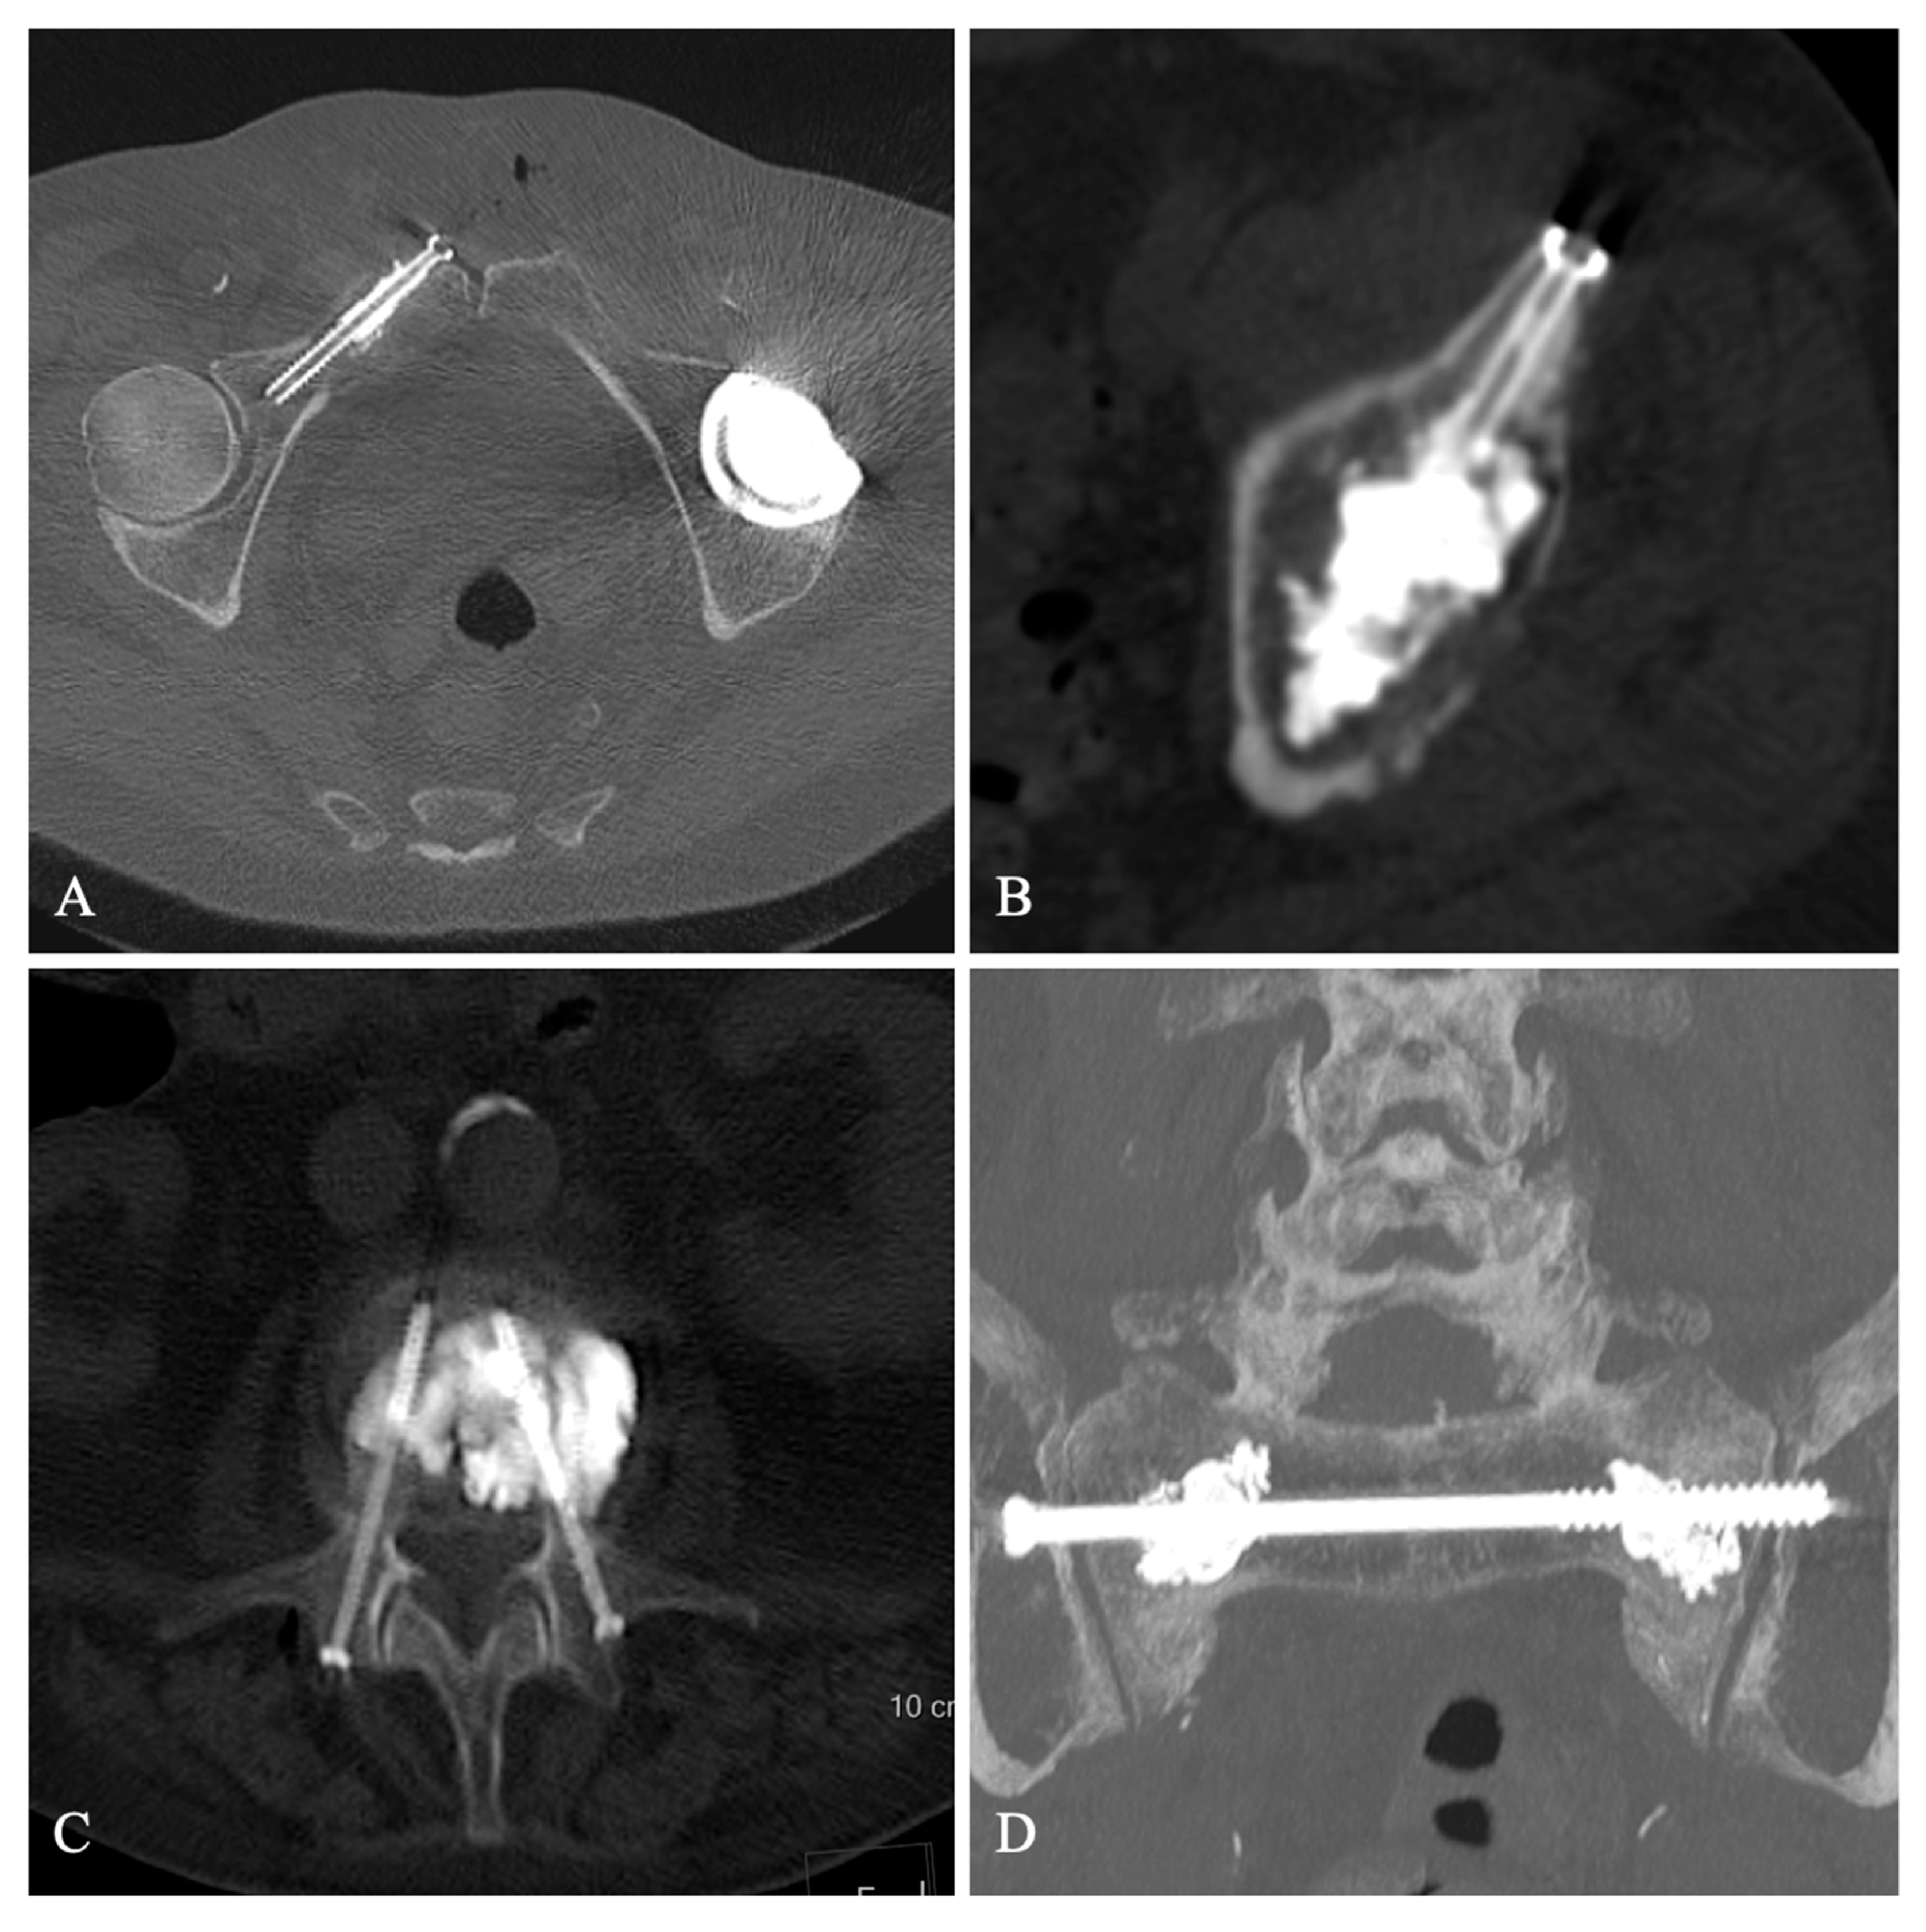

Thirteen patients underwent POS procedures in our department between January and September 2020. Thus, no patient objected to the use of their data for research purposes. One patient was lost because she developed COVID-19 lung disease before the 3-month follow-up visit, which unfortunately led to her death. Eventually, 12 patients were included in the study, 6 males and 6 females (mean age 81 years, range 31 to 95 years), who received percutaneous screw fixation using one (n = 6) or two (n = 6) screws, combined with complementary cementoplasty (n = 11). The indications for POS were as follows: 9 insufficiency fractures; 8 vertebral fractures (4 lumbar and 4 thoracic) with osteonecrosis and monopedicular (n = 3) or bipedicular (n = 5) fracture. They benefited from vertebroplasty with either a single or a bilateral pedicle screwing. One sacrum fracture was treated by sacroplasty and transiliac screw osteosynthesis. One traumatic fracture of the acetabulum was treated with an anterior two-screw fixation and two pathological fractures, one fracture of the ilium–pubic branch on pulmonary metastasis, and one fracture of the acetabulum on myeloma was treated with cementoplasty and single-screw osteosynthesis (Figure 1). The characteristics of the population are shown in Table 1.

Figure 1.

Screw fixation of a right iliopubic branch metastasis (A), Screw fixation of a myeloma lesion of the left acetabulum (B), Bipedicular screw fixation with cementoplasty of an osteoporotic vertebral fracture with osteonecrosis (C), Transiliac screwing with sacroplasty of an insufficiency sacral fracture (D).